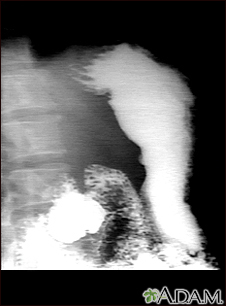

Stomach ulcer, X-ray

This is an example of a procedure called an upper GI series. The person swallows a substance called barium which allows for illumination of the organs in question. In this case, an ulceration is present in the stomach, seen on the right of the screen. This method is a means of diagnosing stomach ulcers as well as other anomalies along the upper gastrointestinal tract.